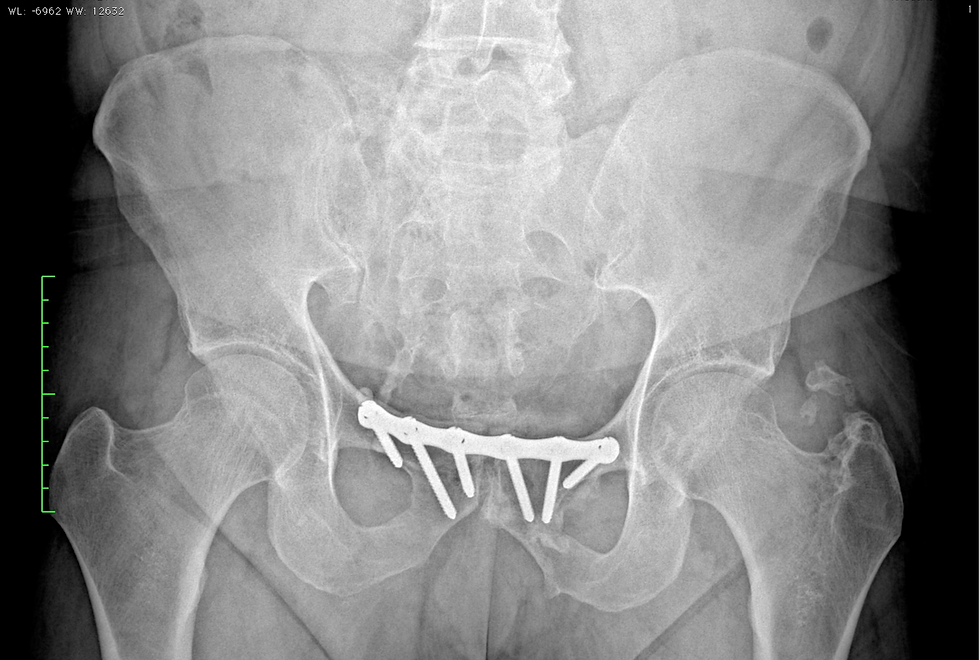

Risultato della stabilizzazione della frattura sacrale, mediante l’applicazione di viti ileo sacrali e placca della sinfisi pubica.

Risultato radiografico dopo 35 anni dall’intervento e dalla rimozione delle viti ileosacrali e dell’infibulo femorale.